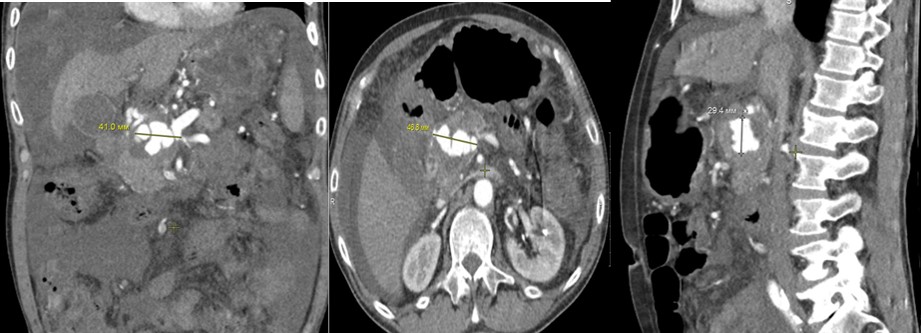

Рис. 2. КТА. Артериальная фаза. Визуализация объёмного образования головки поджелудочной железы с указанием размеров в трёх плоскостях.